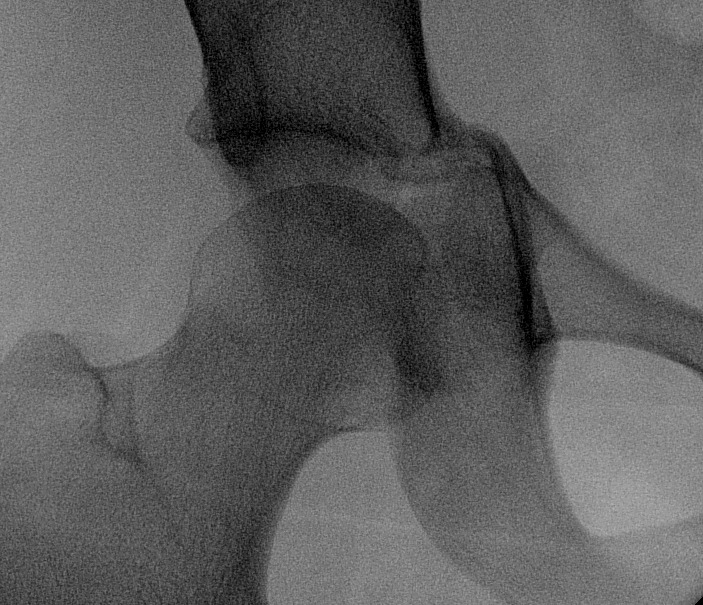

Anterior Column & Wall Fracture

Position

- radiolucent table

- IDC to decompress bladder

- IV Abx

- sandbag under operative side for some elevation

- need to prep and drape pelvis so can virtually access both ASIS

- often need to get across pubis

Ilioinguinal approach

Curvilinear incision from above pubis to ASIS

- identify and protect LFCN / below ASIS

- divide external oblique 1 cm above inguinal ligament

- identify and protect spermatic cord / round ligament

- divide posterior wall / internal oblique and transversus

3 windows (medial / middle / lateral)

- find external iliac artery and vein with peanuts / place sling

- find psoas and femoral nerve / place sling

- find iliopectineal fascia between vessels and psoas and divide with scissors

Medial window medial to vessels

- superior pubic rami

- may have to release some of rectus

Beware corona mortis

- anomolous vascular connection

- 10 - 15% patients

- between external iliac / epigastric artery

- to obturator artery

Middle window between psoas and vessels

- exposes quadrilateral plate

Lateral window lateral to psoas

- elevate iliacus off crest to expose fracture in iliac wing

- exposes around to SIJ